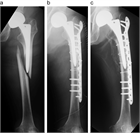

1. ⼈⼯股関節置換術(total hip arthroplasty、THA)後⾻折は種々の外⼒により発⽣するが、minor traumaによるものが多く、その発生率は一次THA後で約3.5%と報告されており、THA施行数の増加に伴い今後さらに増加すると予測される。

1. ステムの固定性が良好である場合は、ロッキングプレート、Dall-Miles cable grip system、ワイヤー、スクリューを用いた骨接合術が推奨される(推奨度1)

1. ステムに弛みを認める場合は、再置換術と骨接合術を行う(推奨度1)